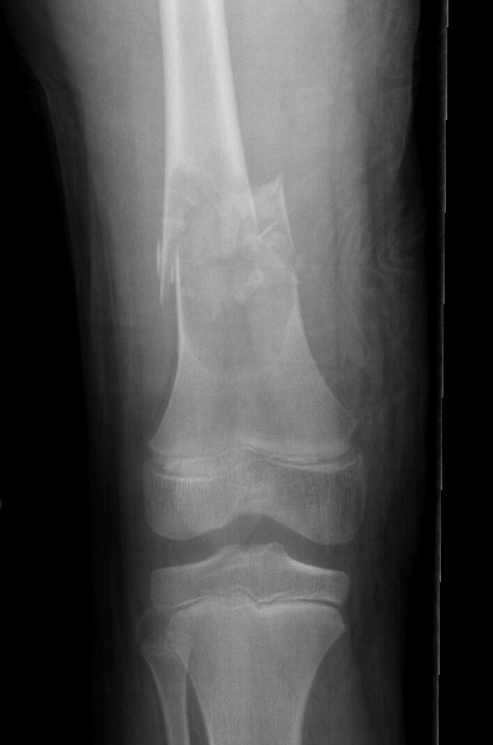

X-ray

Well-defined lucency

- thin sclerotic rim

- usually central

- thinned cortex with slight expansion

- thin internal septa

- can be multi-loculated

Fallen-Leaf (AKA fallen-fragment)

- with pathological fracture

- indicates that the lesion has no matrix and is fluid filled

Fallen leaf sign

DDx ABC